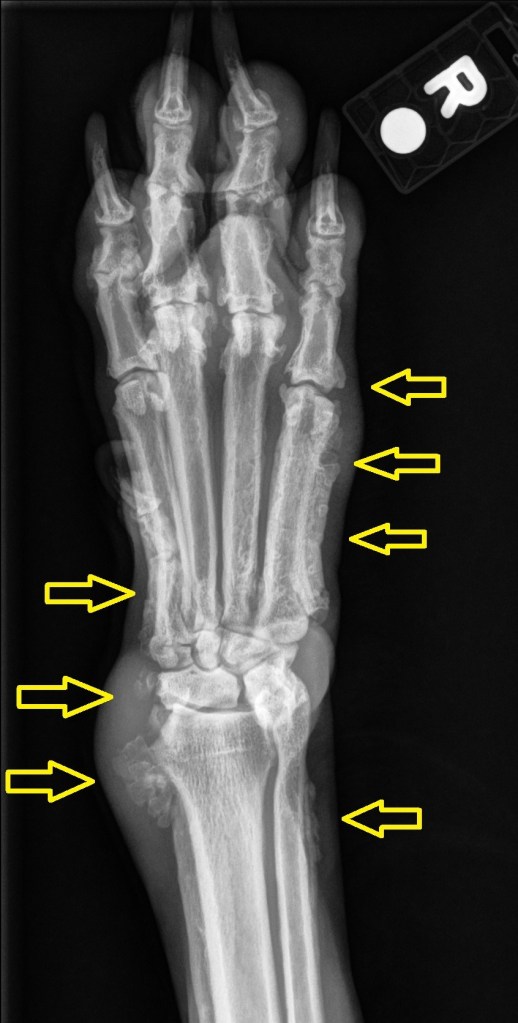

Findings:

Well-defined columnar/palisading periosteal new bone with swollen surrounding soft tissues can be seen along the abaxial surfaces of the diaphyses of the (bilateral) 2nd and 5th metacarpal bones (and the proximal and abaxial aspects of the adjacent proximal phalanges), the distolateral aspect of both ulna, distomedial aspect of both radii, and the medial aspect of both intermedioradial carpal bones.